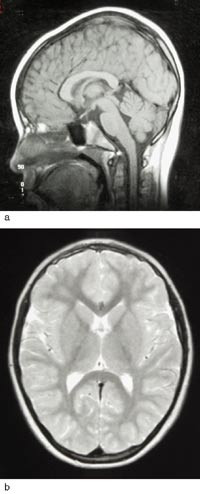

Etter start av pyridoksintilførsel byrja ei rask motorisk og mental utvikling. Ho kunne gå ved 18 månaders alder. Ved 16 månaders alder hadde ho enkeltord, 37 månader gamal 5 – 6 ords setningar. Frå 3 1/2 års alder vart det observert problem med balanse og grovmotorikk. Ho vart reinsleg og tørr i fireårsalderen. Hovudomkrinsen låg i seks månaders alder 1 cm under 2,5-percentilen, under pyridoksinbehandling auka han gradvis til 25-percentilen. Cerebral MR var normal ved vel åtte års alder (fig 2). Fem år og åtte månader gamal viste ein ikkje-verbal evnetest samsvar mellom kronologisk alder og mental utvikling. Ho går no i vanleg skule og fylgjer klassetrinnet sitt. Men ho har slite med språklege og matematiske omgrep – lese-, tal- og mengdeforståing.

Det finst ingen diagnostiske laboratorietestar. EEG kan vise teikn på diffus og fokal cerebral dysfunksjon, men ingen spesifikke mønster (4). Cerebral CT og MR har vist uventa høg prevalens av strukturelle defektar i sentralnervesystemet, men ingen typiske abnormitetar. Det er funne varierande grad av atrofi av grå og kvit susbstans og tynn corpus callosum, som hjå vår pasient, likeins cerebellar hypoplasi og mega cisterna magna (8, 10). Inadekvat pyridoksinbehandling synest å kunne medføre progredierande atrofi av grå og kvit substans (10).

Ubehandla døyr pasienten i ein alvorleg krampetilstand. Alderen ved dødstidspunktet hjå 31 ubehandla pasientar varierte mellom to dagar og 16 månader, gjennomsnittleg 3 1/2 månad (13). Prognosen ser ut til å vere betre hjå dei som debuterer etter ein månads alder (3). Det synest å vere ein viss samanheng mellom prognosen og tidsromet frå krampedebut til behandlingsstart. Ved tidleg krampedebut er meir enn ei vekes behandlingsutsetjing assosiert med aukande fare for utvikling av lærevanskar og cerebral parese. Vår pasient illustrerer at prognosen kan vere god når pyridoksindoseringa er adekvat, sjølv om behandling vart starta relativt seint. I eit nordengelsk materiale med seks pasientar lærde borna å gå då dei var mellom 12 og 40 månader gamle, og dei byrja å tale då dei var mellom 12 og 36 månader. Ingen utvikla cerebral parese, men dei fleste hadde ekspressive språkvanskar, men relativt intakt språkforståing. IQ varierte frå under 50 til 90 (8). Dersom pyridoksintilførselen er for låg eller uregelmessig, kan det oppstå hjerneatrofi og forseinka utvikling av alvorleg grad (10). Utviklinga hjå vår pasient kan tyde på at høg pyridoksindose kan føre til ei positiv utvikling, bedømt både klinisk og etter cerebral MR (fig 1, fig 2).